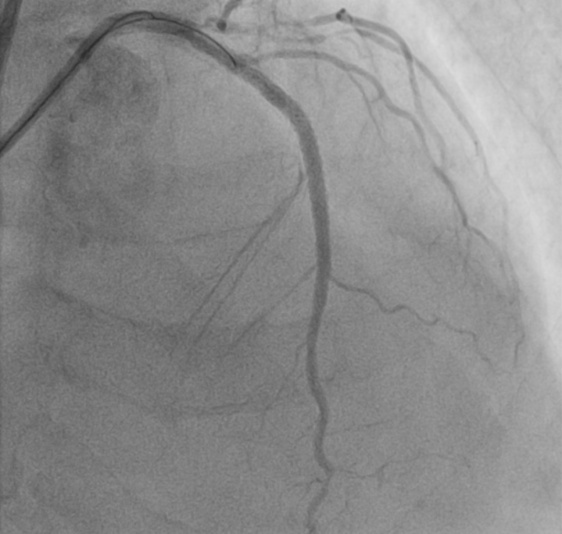

时间就是生命,每一分每一秒都关乎患者安危。抵达医院后,心血管内科在刘学波主任的指挥下迅速响应,医护人员第一时间投入到紧急救治工作中。王明的治疗难度极大,因多年患有糖尿病,心脏三根主要血管均存在重度弥散性钙化病变,外周血管状况也差,且肾功能不全、贫血。经过纠正心衰治疗病情相对稳定后,1月13日,在前期充分的药物治疗基础上,刘学波、来晏、姚义安、钱军等医生对患者行冠脉造影术,提示心脏三根冠脉均存在重度狭窄。其中最重要的左前降支为重度钙化病变,并且术中患者血压偏低,医护人员当机立断,为患者植入主动脉内球囊反搏(iabp),针对严重钙化的血管,来晏主任医师精准运用冠脉内冲击波碎石术(震波球囊)等专业技术破解治疗难题,成功在左前降支植入支架,有效疏通狭窄血管,手术全程顺利,为患者生命安全奠定坚实基础。

支架术后